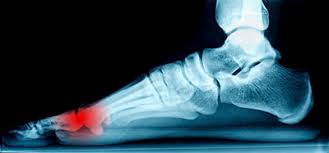

피로 골절이 자주 생기는 부위

피로 골절은 반복적으로 체중이 실리는 부위에서 흔히 발생합니다. 특히 아래 부위는 비교적 자주 언급됩니다.

• 발등과 발바닥 앞쪽

• 정강이 뼈 주변

• 발목과 뒤꿈치 근처

• 장시간 서 있거나 걷는 경우 무릎 아래 부위